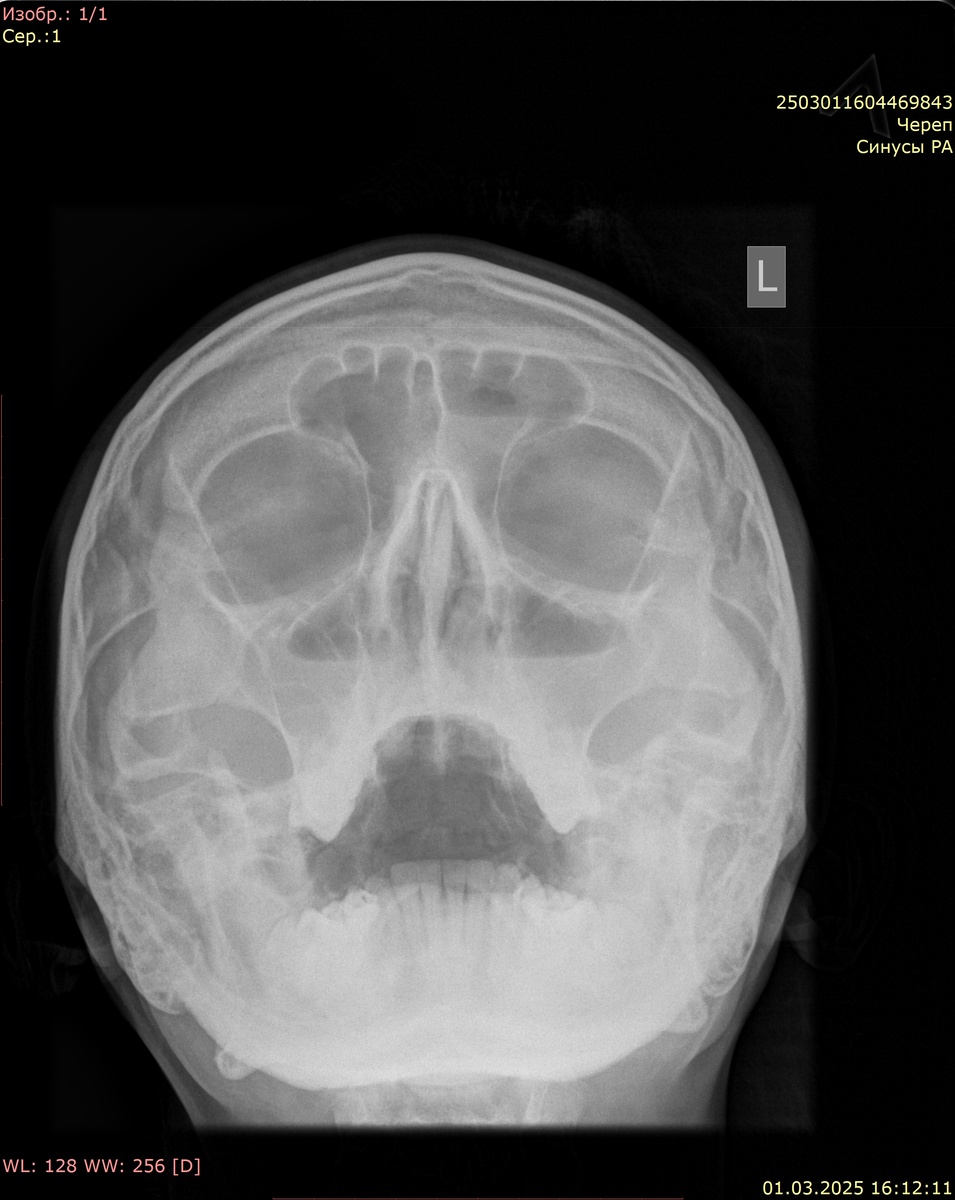

Обзорная рентгенография придаточных пазух носа:

Визуализируются придаточные пазухи носа: верхнечелюстные, лобная, ячейки решетчатого лабиринта, клиновидная. Контуры пазух четкие, ровные. В обеих в/ч пазухах определяется горизонтальный уровень жидкости до 1/2 с утолщением стенок. В левой лобной пазухе также горизонтальный уровень жидкости до 1/2. Носовая перегородка по средней линии.

Заключение: картина двустороннего экссудативного в/ч синусита с уровнями жидкости до 1/2. Левосторонний фронтит с уровнем жидкости